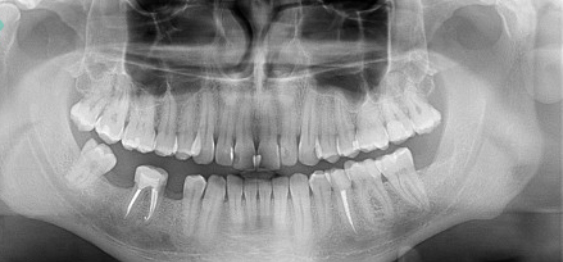

X-ray panoramic image (Panoramic / Panorama)

Used by dentists to define an endodontic, implantological, surgical and orthodontic treatment plan. Often referred to as a “tooth panorama” or as a panoramic image. Pantomographic dental x-ray enables early detection of pathological changes in the bones of the maxilla and mandible, as well as in the temporomandibular joints and maxillary sinuses.